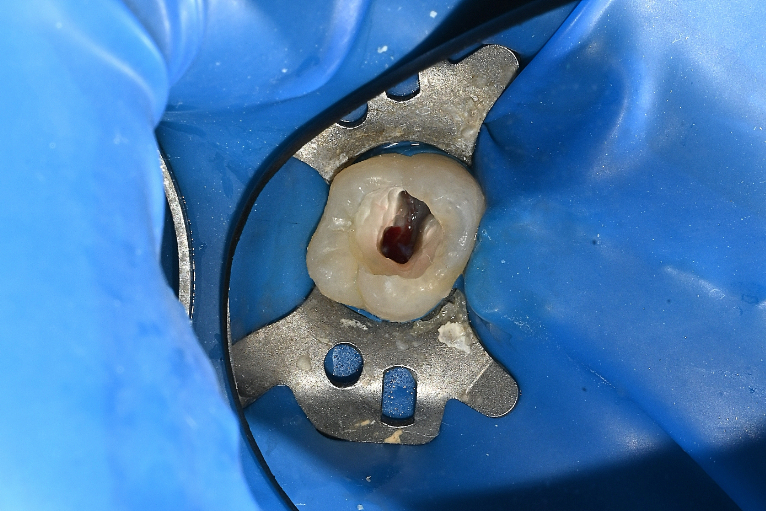

ラバーダム防湿

正常歯髄をMTAセメントで保存

| 治療説明 | 歯髄に到達する大変大きな虫歯がありました。まだ若い患者であり、通常通り根管治療を行うと、歯質が薄くなり歯の寿命に大きく影響すると考えました。う蝕と感染の疑いがある歯髄を除去し,正常歯髄をMTAセメントを用いて保存した上で、ダイレクトボンディングにて歯の形を回復しました。 |

| 治療回数・期間 | 1回 |

| 副作用とリスク | 歯髄が感染し根管治療が必要となる可能性があります。レジンの着色、破折が起こり、研磨や再修復が必要となる可能性があります。 |

| 料金(税込) | MTAセメント:55,000円 ダイレクトボンディング:55,000円 |